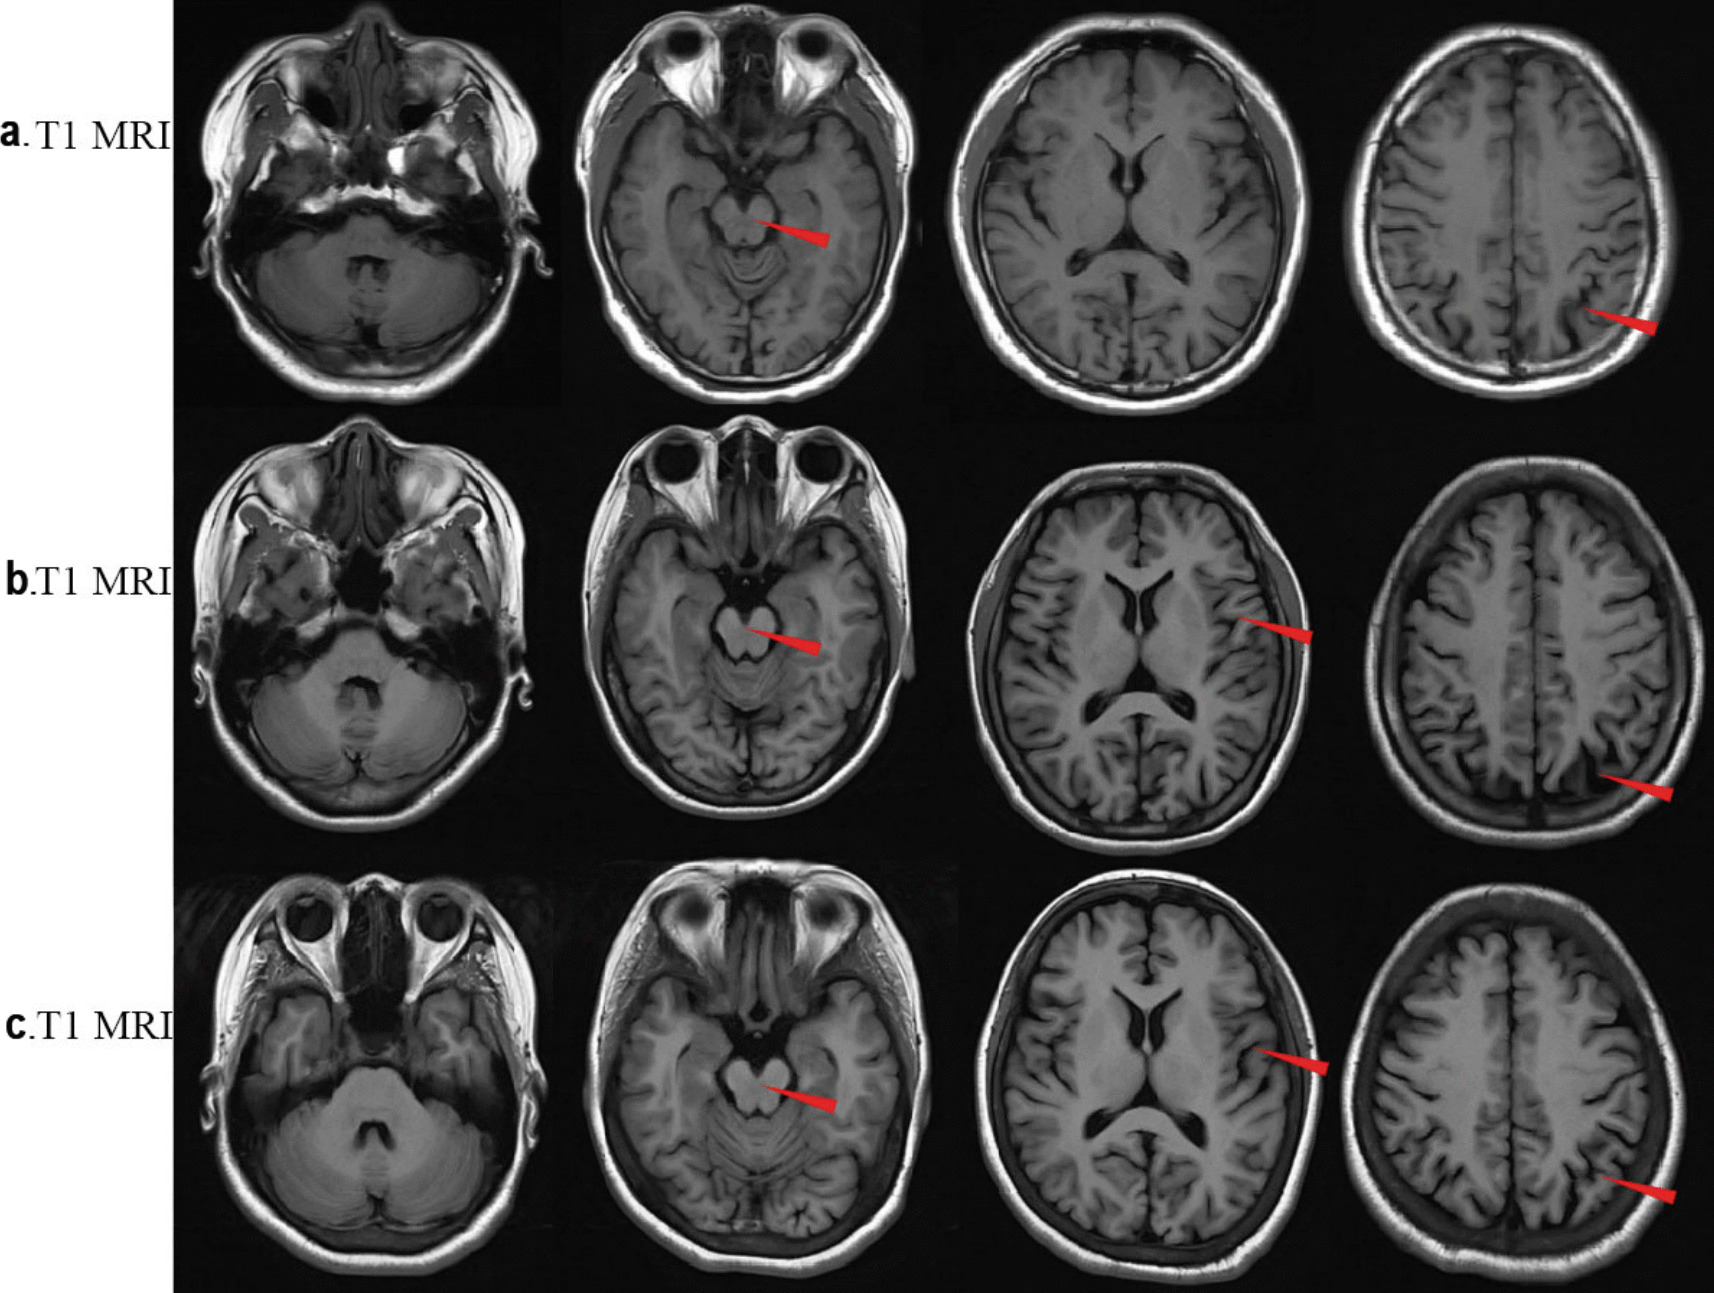

Case presentation: Here, we report a case involving a patient and his two sisters, all of whom showed seizures and ataxia during adolescence, with progressively worsening symptoms. Prior to admission, none of the patients had received a systemic diagnosis or treatment. The whole exome sequencing identified a homozygous NEU1 mutation (NM_000434.3:c.544A > G [p.Ser182Gly]) in all three siblings. Their parents and children, who were asymptomatic, were found to be heterozygous carriers. The three patients were ultimately diagnosed with type I sialidosis and treated with antiseizure medications, but they continued to experience recurrent seizures.